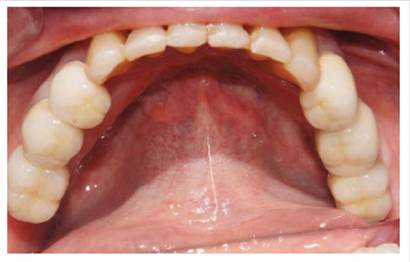

Luego se procedió a la fabricación de la estructura metálica del maxilar superior con la ayuda de una pantalla de silicona obtenida del protocolo reverso, esta estructura presentó un asentamiento pasivo comprobado clínica y radiográficamente luego de realizar los cortes y soldajes necesarios (Figura 5). Se realizó el enfilado para la prótesis híbrida con dientes Ivostar/Gnathostar donde se evaluó estética y fonación. En el maxilar inferior se torquearon los pilares CM recto para la pieza 35 y Pilares angulados (17°) a nivel de piezas 36 y 46 fresados con la ayuda de una guía de colocación de pilares (Figura 6) y se fabricaron coronas de metal cerámica. Para finalizar se procede a la instalación de la prótesis híbrida superior, la cementación de las coronas con cemento temporal y la instalación de una férula de DCM (figura a y b). Finalizado el tratamiento se realizaron controles periodontales y protésicos periódicos donde se comprobó la correcta concientización del paciente en cuanto a su mantenimiento. (Figura 8)